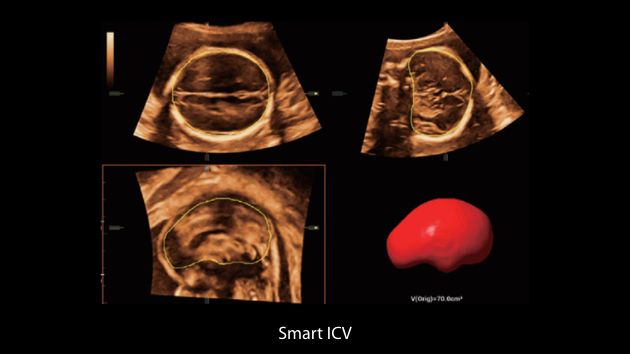

Nuewa I9, kad?nlara ve yenido?anlara y?nelik sa?l?k hizmetleri i?in ?zel olarak tasarlam??t?r ve i?ten d??a yenilik?i bir deneyim sunmaktad?r. Bu yenilikler, karma??k klinik senaryolara ili?kin derinlemesine bilgilere dayal? olarak geli?tirilmi?tir ayr?ca do?ru ve zaman?nda yan?tlar?n yan? s?ra, ola?an├╝st├╝ verimlilik ve ola?an├╝st├╝ kullan?c? deneyimi sunar.